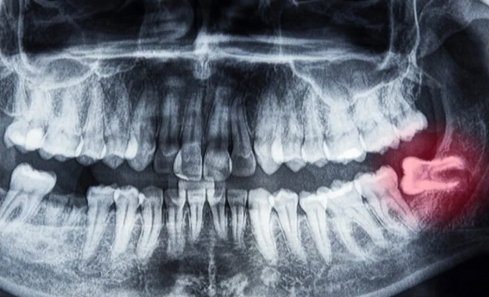

Wisdom Tooth extraction a surgical procedure to remove one or more wisdom teeth , located at the back corners of your mouth on the top and bottom.

• If a wisdom tooth doesn’t have room to grow, results in pain, food entrapment, infection or gum disease, tooth decay infection or other dental problems, you’ll likely need to have it pulled.